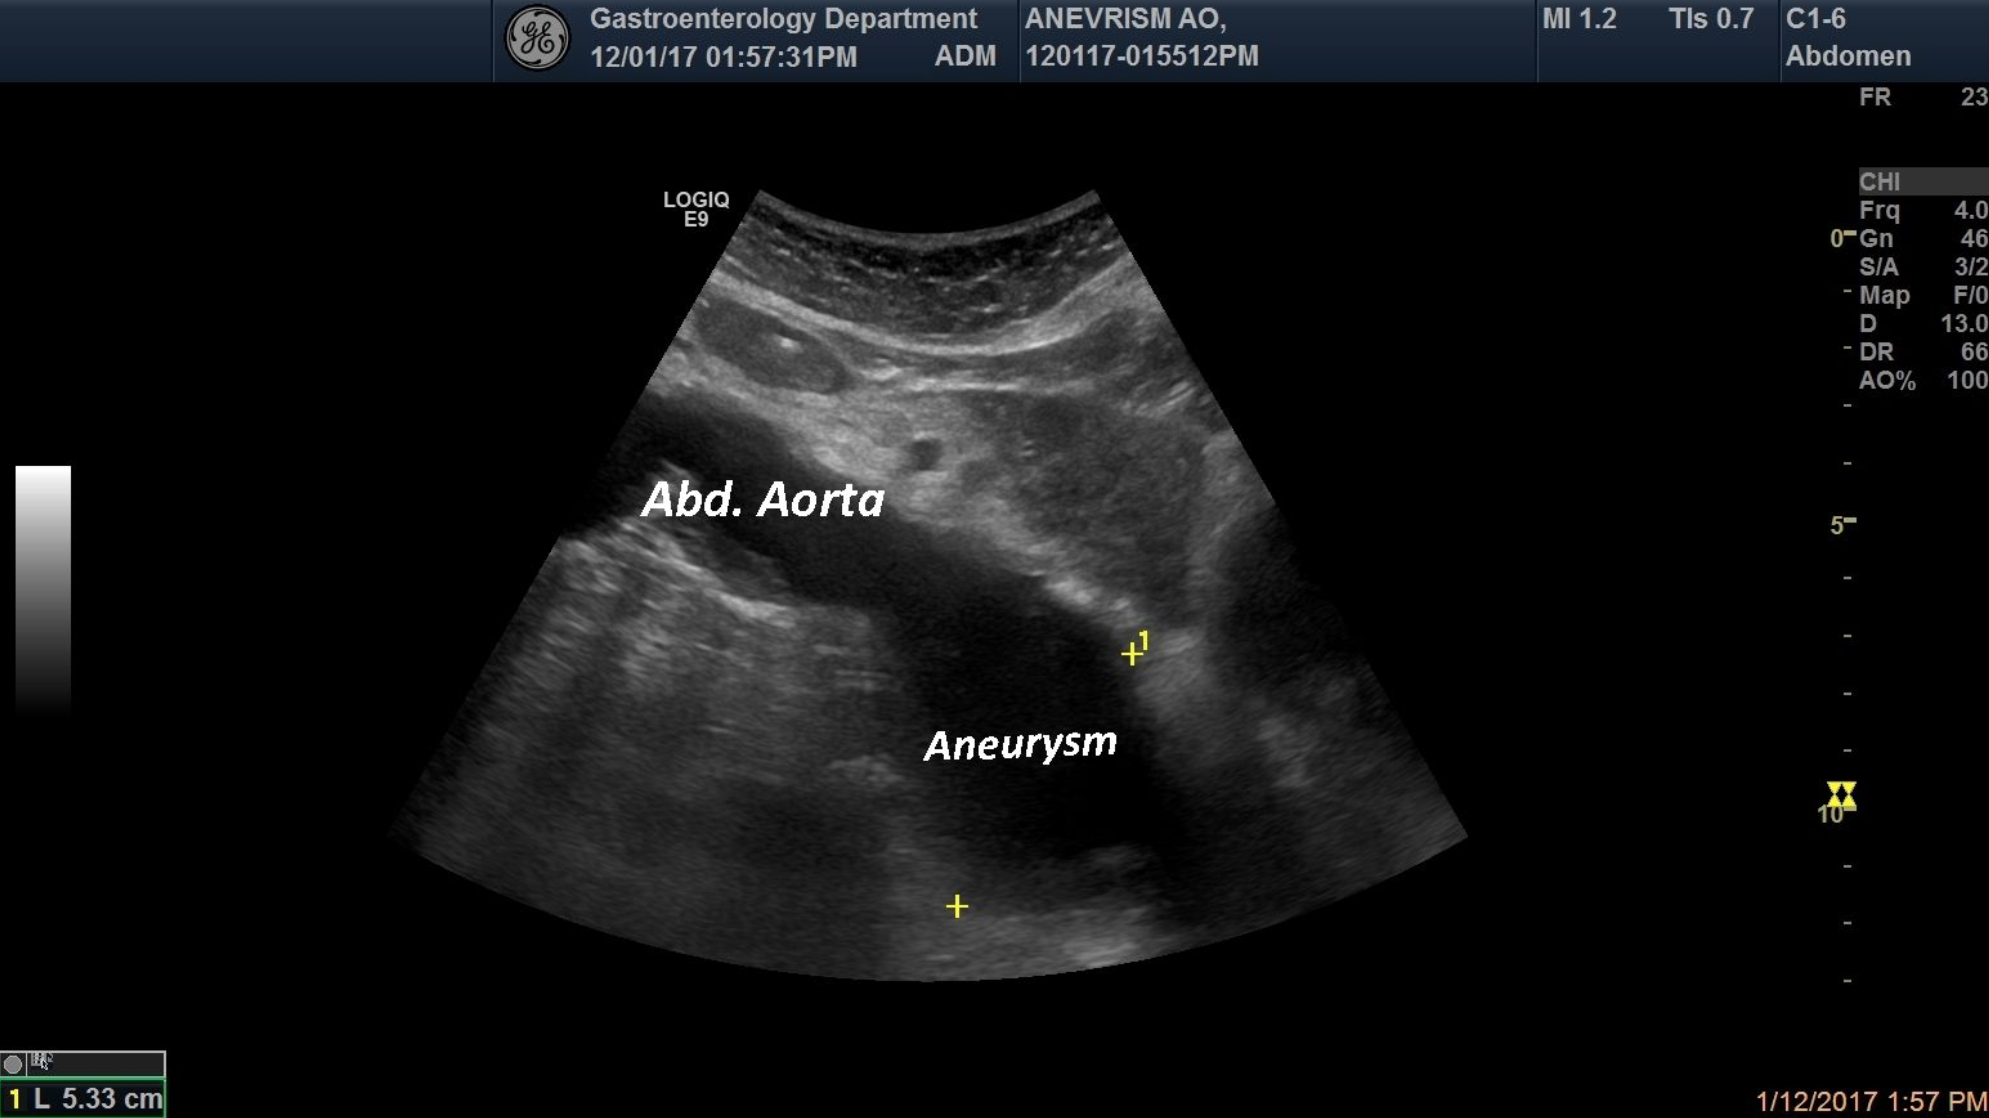

Abdominal Aorta Aneurysm [1 image] Categories Abdominal vesselsAortaBASIC ULTRASOUND IMAGES TITLE: Abdominal Aorta Aneurysm DESCRIPTION: In this picture the Abdominal Aortais displayed, where anAorticAneurysmof 5.3 cm is seenin an asymptomatic patient. EMAIL CONTACT:moga.tudor@yahoo.com KEYWORDS:Aorta, Aneurysm Related postsJanuary 5, 2021Walled-off pancreatic necrosis [2 images]Read more